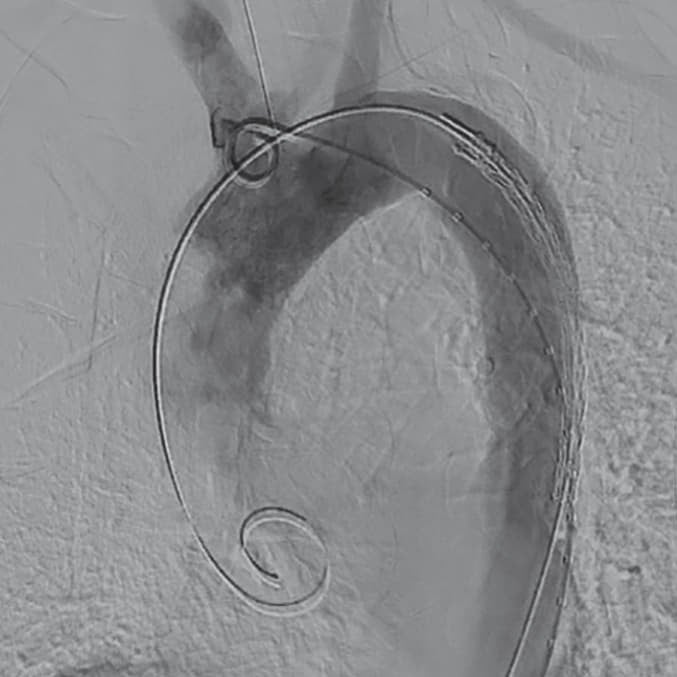

慢性スタンフォードB型大動脈解離に対するゴア

®

TAG

コンフォーマブル 胸部大動脈ステントグラフト アクティブコントロールシステム

さらに詳しく